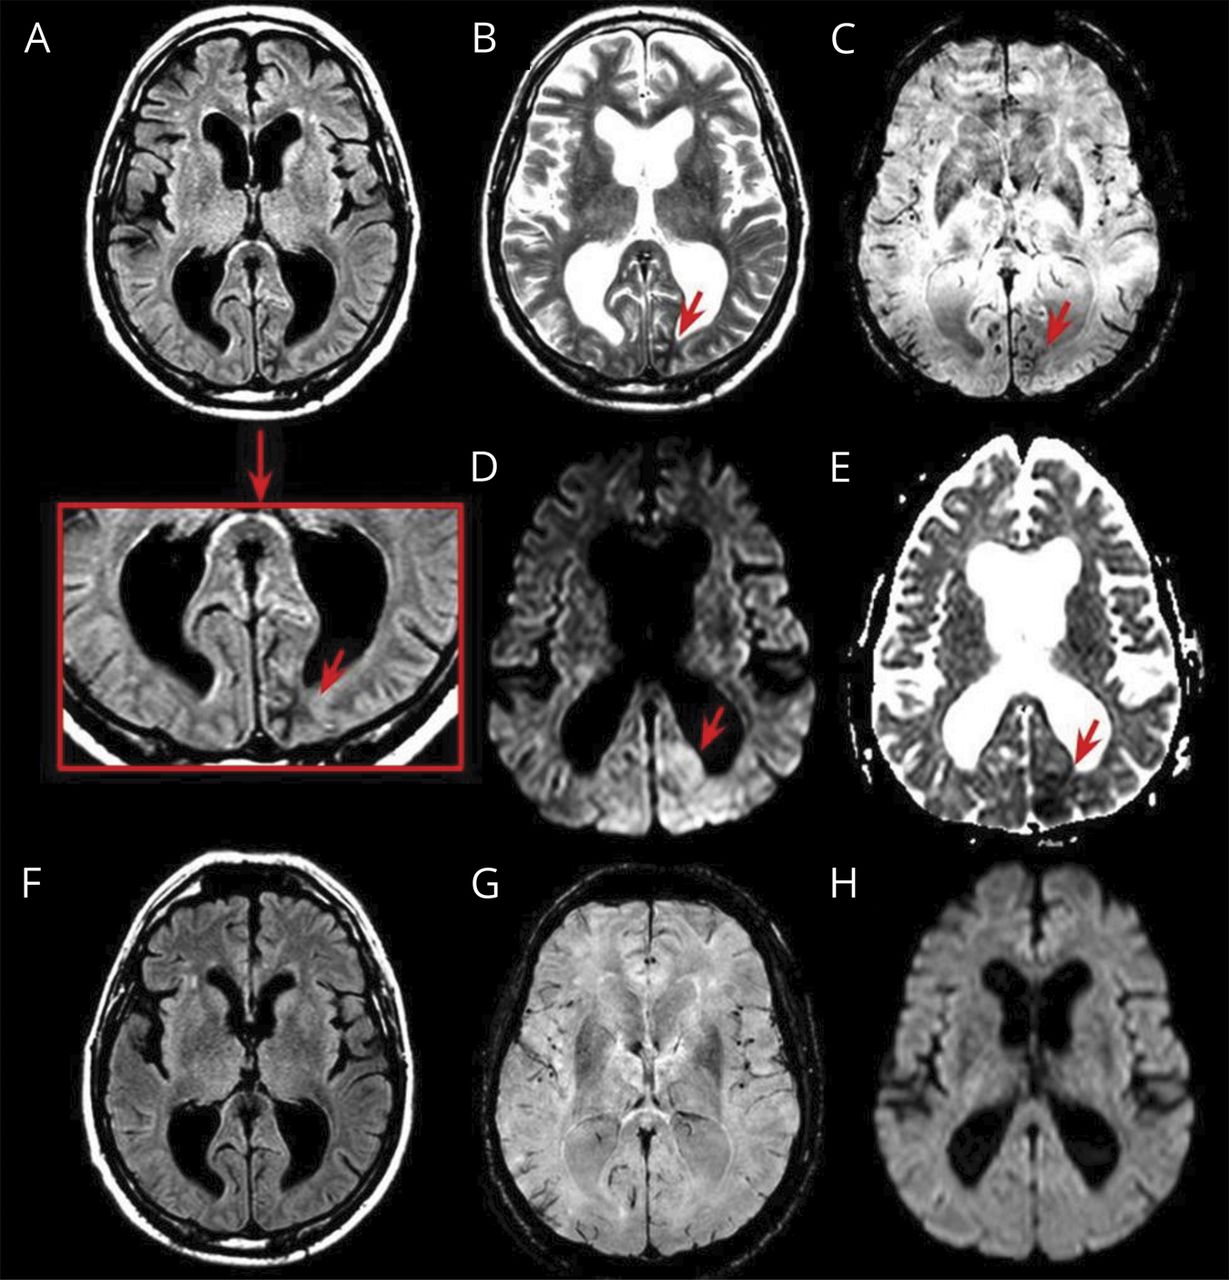

图

枕MRI改变nonketotic高血糖的hyperosmolar状态

入院时,脑部MRI显示左皮层下枕hypointense fluid-attenuated反转恢复损伤,T2,susceptibility-weighted成像地图,表观扩散系数(A - c和E)和hyperintense diffusion-weighted成像(D)。一个控制脑部MRI表现在3个月是正常的(F-H)。